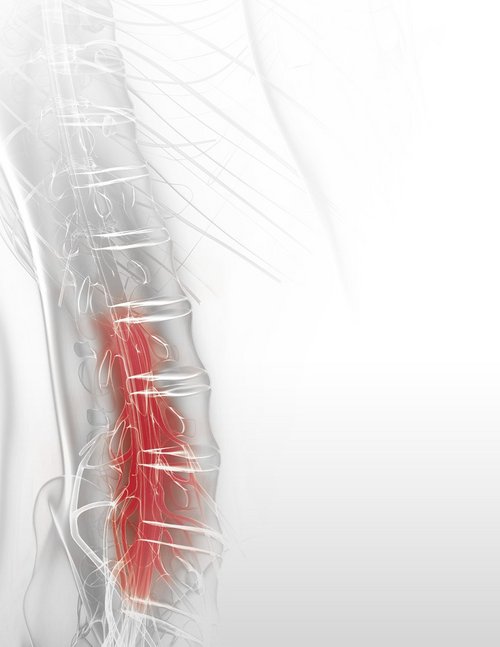

A herniated disc, where part of the disc protrudes through a tear in its outer layer and compresses nearby nerve structures, can cause various problems. This can lead to pain, numbness, or weakness. Treatment options include physiotherapy, pain management, and, in severe cases, surgery.

Location of the Herniation